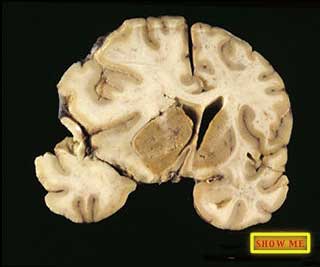

Can you find indications of some of the brain swelling that was responsible for her death?